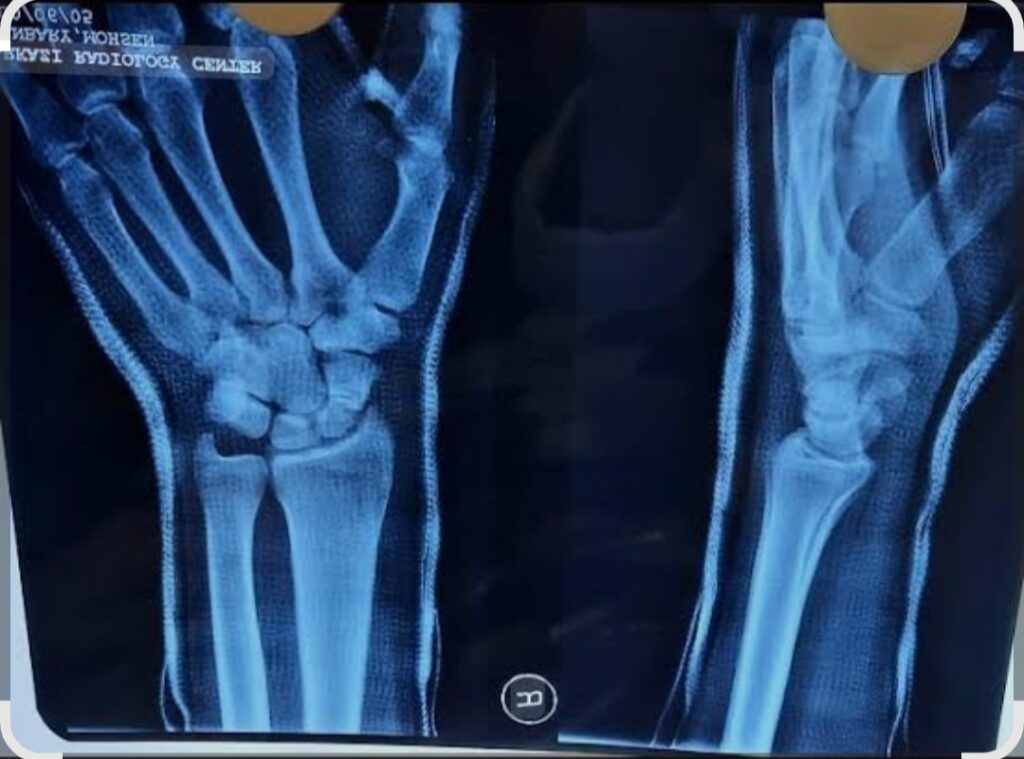

برای تشخیص شکستگی اسکافوئید، پزشک در ابتدا از رادیوگرافی ساده استفاده میکند. با این حال، از آنجا که خط شکستگی در بسیاری از موارد بسیار ظریف میباشد، عکسبرداری اولیه همیشه قادر به نشان دادن آن نیست. به همین علت توصیه میشود اگر بیمار همچنان درد و حساسیت در مچ داشت، بعد از یک تا دو هفته مجددا تصویربرداری انجام شود.

در مواردی که نیاز به بررسی دقیقتر وجود دارد، انجام امآرآی (MRI) بهترین گزینه محسوب میشود. این روش میتواند حتی ترکهای بسیار کوچک را آشکار کرده و علاوه بر آن، وضعیت خونرسانی استخوان اسکافوئید را نیز نشان دهد. این مزیت اهمیت زیادی دارد چرا که خونرسانی محدود اسکافوئید عامل اصلی بسیاری از عوارض احتمالی میباشد.

در کنار این روشها، سیتیاسکن (CT Scan) نیز روش بسیار خوبی است که دقت بسیار زیادی در نمایش جزئیات شکستگی و میزان جابهجایی قطعات استخوان دارد. پزشکان اغلب برای برنامهریزی جراحی و یا تصمیمگیری در مورد بهترین نوع درمان از این روش استفاده میکنند.